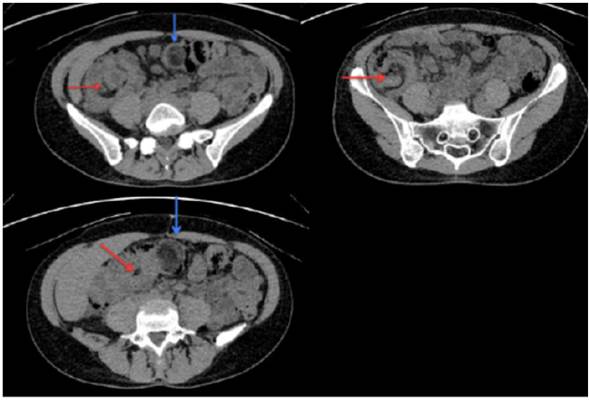

Se sospechó entonces que el dolor estuviera causado por una urolitiasis, por lo que se solicitó tomografía abdominal simple con protocolo en decúbito prono, en la que se evidenció imagen de intususcepción ileocecal con extensión hacia el colon trans verso y lesión sólida con densidad grasa que sugería lipoma intestinal en la cabeza de la intususcepción; no evidenciándose signos de obstrucción intestinal (Figura 1).

Figura 1 TAC simple de abdomen. La flecha roja señala el lipoma que actúa como punta de lanza a la cabeza de la intususcepción. La flecha azul evidencia la lesión en diana característica, la cual avanza hasta el colon transverso.